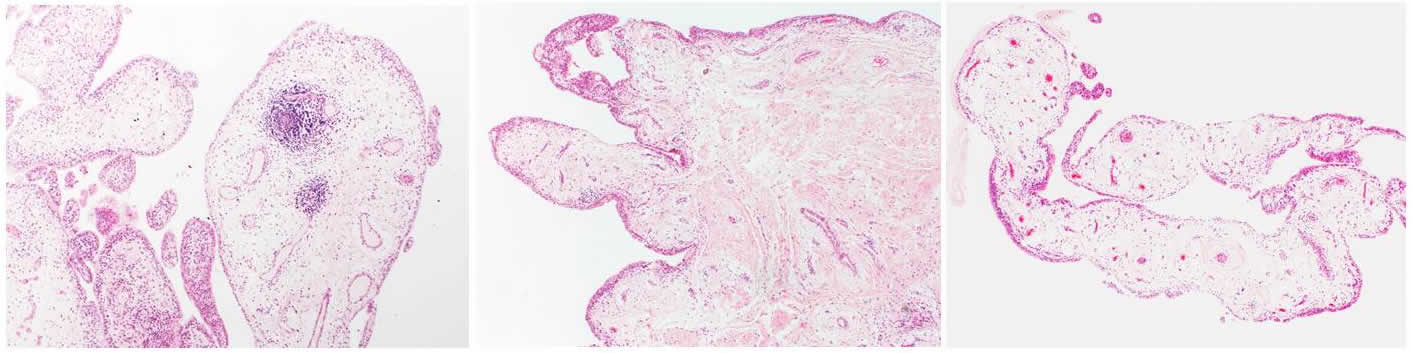

Different B cell types can be investigated by analysing a synovial biopsy, where small pieces of tissue of an inflamed joint are taken for examination under a microscope.